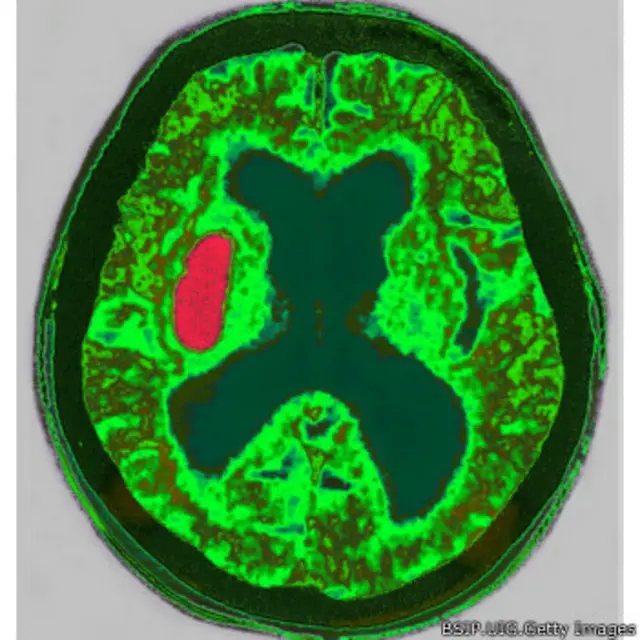

خونریزی مغزی

خونریزی دلیل دیگری برای افزایش فشار داخل جمجمه است. خونریزی میتواند در داخل بافت مغز یا بطور شایعتر در رگهای بین مغز و جمجمه (Subdural haematoma) اتفاق بیفتد.

زمانی که ضربه به سر باعث جابجا شدن مغز میشود ممکن است رگی در مغز پاره شود اما علائم آسیب مغزی ممکن است بلافاصله ظاهر نشود و چند ساعت یا حتی چند روز طول بکشد.

خونریزی که ادامه پیدا کند فشار داخل جمجمه زیاد میشود و چون جمجمه نمیتواند بزرگ شود در نتیجه به بافت مغز فشار وارد میشود. بافت مغز زیر این فشار به تدریج له میشود و به عملکرد عصبی آن آسیب جدی وارد می آید. تقریبا در اکثر این موارد باید با جراحی فشار را کم کرد.